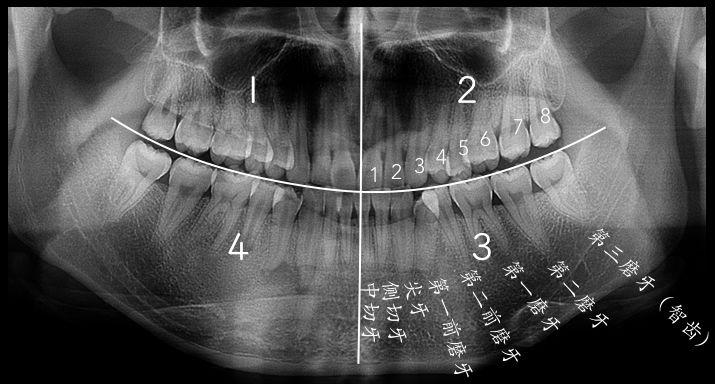

智齒的形態(tài)拔智齒的收費(fèi)依據(jù)價(jià)格的背后——牙醫(yī)知識(shí)的凝聚常見智齒的形態(tài)智齒是從正中的門牙往里數(shù)第八顆牙齒,也就是第三顆磨牙。它是發(fā)育、萌出晚的牙齒,通常在4~5歲時(shí)形成牙胚,隨后逐漸發(fā)育形成牙齒,一般17~25歲左右萌出,此時(shí)人的生理、心理發(fā)育都接近成熟,因此俗稱“智齒”。

智齒的形態(tài)也是各種各樣,簡(jiǎn)單可以羅列如下幾種,實(shí)際復(fù)雜遠(yuǎn)不止以下:

1、垂直高位

2、舌向高位

3、前傾高位

4、水平高位

5、垂直中位

6、舌向中位

7、前傾中位

8、水平中位

9、垂直低位

10、舌向低位

11、前傾低位

12、水平低位